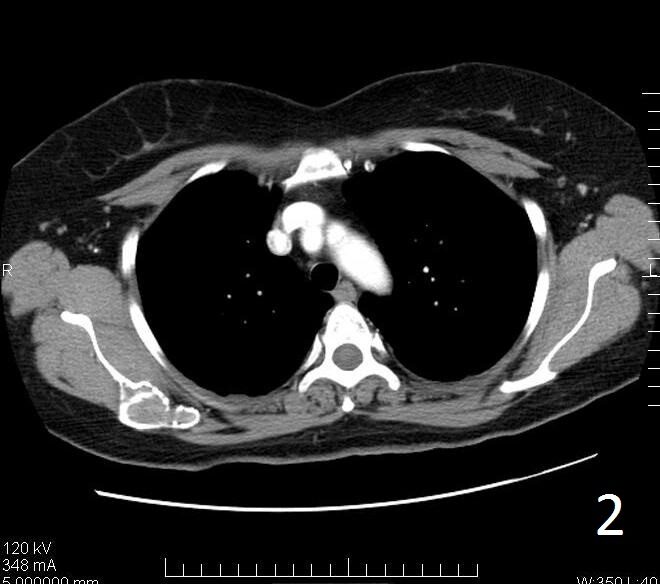

• Useful to determine the extent of the lesion as well as ground glass appearance (Fig. 2-3)

• Well defined borders

• Possible endosteal scalloping lesion

• Areas of mineralization within.

Fig. 2. Axial CT reconstruction of the shoulder illustrates a lytic lesion of the right scapula consistent with fibrous dysplasia. There is a ground glass appearance.